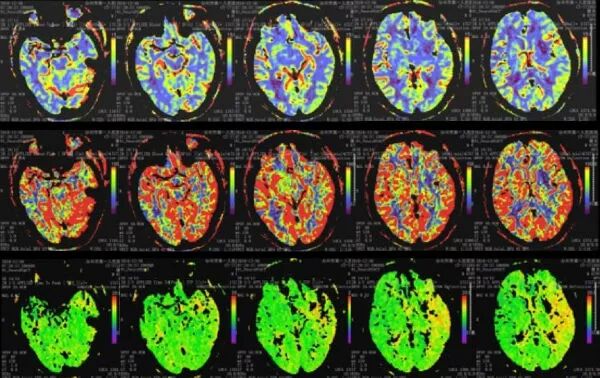

CT平扫未见早期梗死表现;CT灌注成像示:左侧半球MTT延长,CBF见内囊有部分核心坏死,CBV下降不显著。

影像表现与评分不符,图像经MIStar处理后,左侧CBV核心区为4ml,半暗带>15ml。